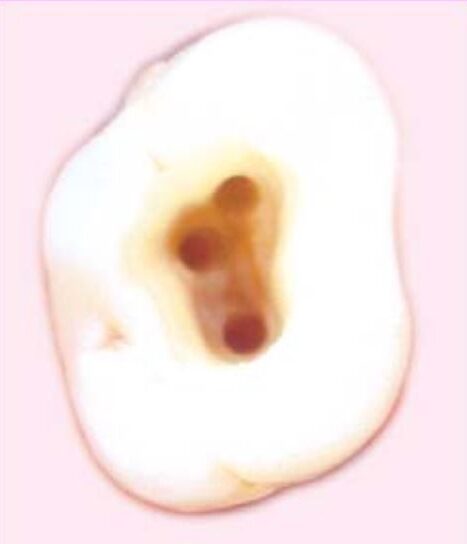

Khi nhìn từ mặt nhai hoặc mặt trong phải thấy rõ tất cả miệng ống tủy (H5.1 a,b).